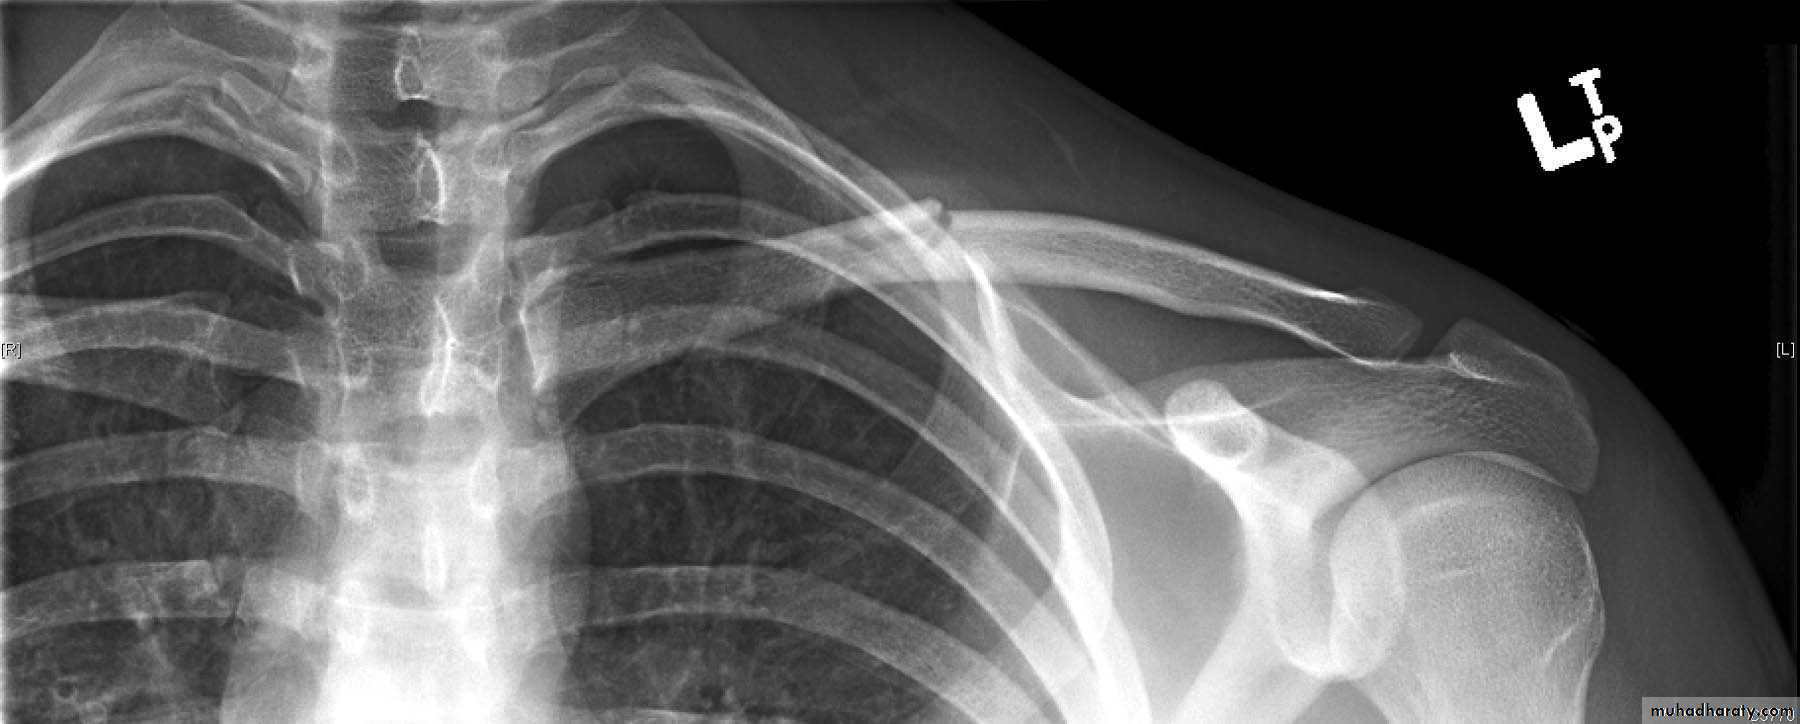

3-The Acromioclavicular joint:

How the AC joint is injured?The AC joint is a quite common sporting injury especially in contact sports. It is usually injured by a fall directly onto the shoulder or a fall onto the arm or a tackle.

The ligaments that bind the clavicle to the acromion are firstly stretched, and thentorn. Depending on the severity of the injury the clavicle can tear away from the acromion causing a noticeable lump to appear on top of the shoulder. The injury results in considerable pain, swelling and loss of shoulder movement.

Grading of an AC joint injury:

The most commonly used classification system recognizes 6 severities of AC joint injury.grade I

A slight displacement of the joint. The acromioclavicular ligament may be stretched or partially torn. This is the most common type of injury to the AC Joint.grade 2

A partial dislocation of the joint in which there may be dome displacement that may not be obvious during a physical examination. The acromioclavicular ligament is completely torn, while the coracoclavicular ligaments remain intact.Grade 3

A complete separation of the joint. The acromioclavicular ligament, the coracoclavicular ligaments and the capsule surrounding the joint are torn. Usually, the displacement is obvious on clinical exam. Without any ligament support, the shoulder falls under the weight of the arm and the clavicle is pushed up, causing a bump on the shoulderGrades I-III are the most common. Grades IV-VI are uncommon and are usually a result of a very high-energy injury such as ones that might occur in a motor vehicle accident.